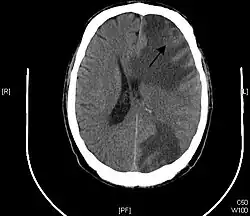

Brain - CT scan - Metastatic Pulmonary Adenocarcinoma. Arrow points to extensive edema of frontal lobe due to 23mm mass. Second area of edema can be seen in the left parietal-occipital region. - Genitourinary tract cancers, 11%

Brain imaging (neuroimaging such as CT or MRI) is needed to determine the presence of brain metastases.[6] In particular, contrast-enhanced MRI is the best method of diagnosing brain metastases, although primary detection may be done using CT.[10] Positron emission tomography (PET) is usually not considered suitable for imaging of brain metastases, because the most frequently used PET-radiotracer, 18F-FDG, does not only accumulate in the tumor but is naturally taken up by normal brain tissue, usually resulting in insufficient tumor-to-background contrast. PET-imaging of brain metastases is however feasible using alternative radiotracers, such as the Gallium-68 labeled peptide 68Ga-Trivehexin,[13] a tracer targeting the tumor cell surface protein αvβ6-integrin. 68Ga-Trivehexin demonstrated high uptake in a brain metastasis of tonsil carcinoma but no uptake in the surrounding healthy brain tissue, enabling a delineation of the brain metastasis (see image).[14]